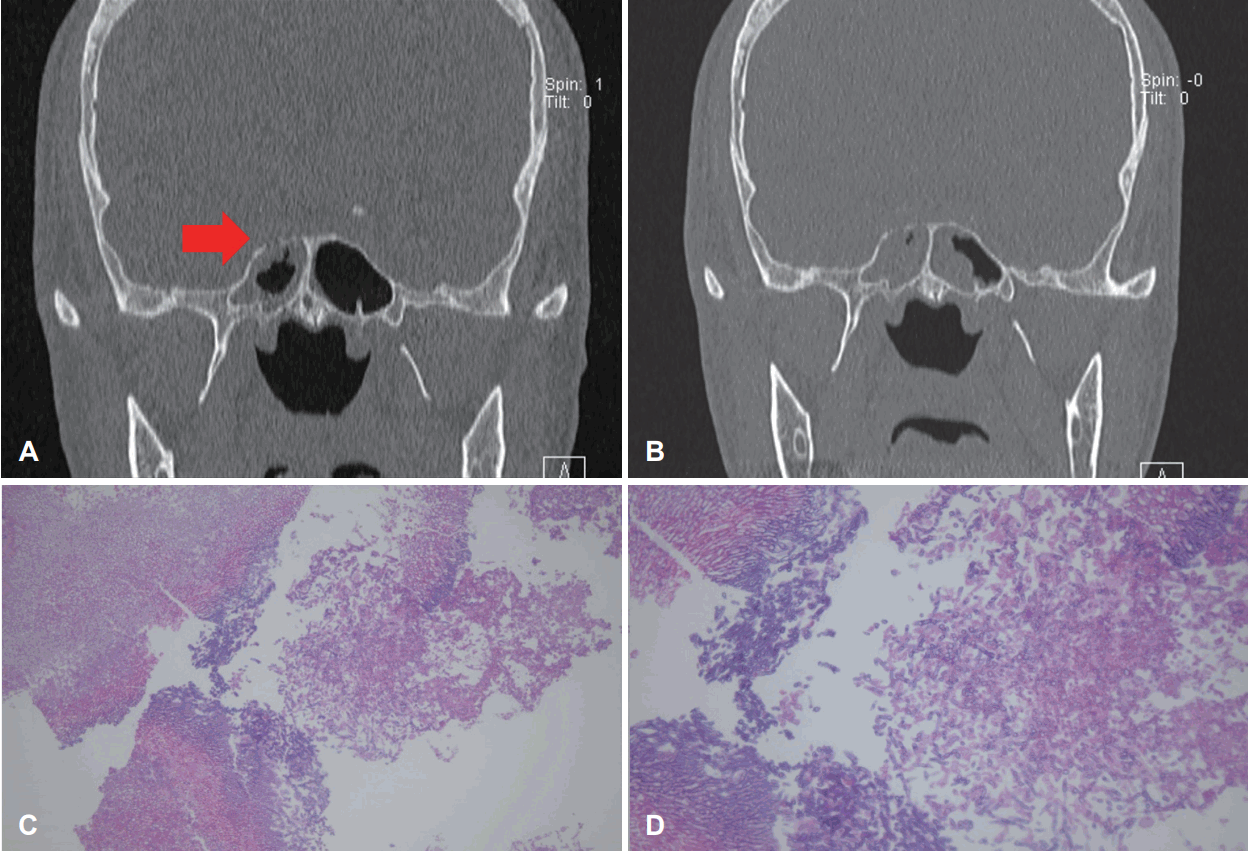

A 58-year-old male was admitted to our hospital for consolidation therapy. He had been in remission from acute myeloid leukemia for 3 months. The patient had suddenly developed persistent fever, headache and facial edema during hospitalization. The hematologist-oncologist suspected fungal infection and consulted with the Department of Otorhinolaryngology. The patient was under diabetes medication, and had received ESS 4 years earlier due to inverted papilloma in the left sinus. There were no specific findings during physical examination, including nasal endoscopy. Paranasal sinus (PNS) CT findings also showed no suspicious lesions that might indicate fungal infection (Fig. 1A-C). Therefore, antibiotics and nasal douching were prescribed for the follow-up period. Five days later, the patient showed chemosis and limitation of the entire visual field in the right eye. Visual acuity measured 0.6 in the right eye and 1.2 in the left eye. On the follow-up PNS CT scan 12 days after the initial scan, sinusitis showed an overall improvement, but the lesion in the right sphenoid sinus remained and the right cavernous sinus showed a density change that indicated obvious obstruction of the right internal carotid artery (ICA) and right cavernous sinus (Fig. 1D and E). Preoperative diagnosis was ‘chronic sinusitis (both),’ ‘orbital apex syndrome (right),’ and ‘suspicion of fungal infection (right).’ Emergency ESS was performed and amphotericin B was initiated with suspicion of mucormycosis. Postoperative brain inner ear MRI with contrast enhancement was performed. This revealed total occlusion in the right cavernous ICA (Fig. 1F). On the 6th day after surgery, invasive aspergillosis was confirmed on biopsy (Fig. 1G and H) and the antifungal agent was changed to voriconazole. Twentyone days after surgery, the patient’s extraocular muscle movement (EOM) was restored to normal, and on the 45th day, endoscopic examination showed no sign of recurrence. A follow-up MRI scan taken 1 month later showed that total occlusion in the right cavernous ICA still existed but mild improvement in thrombophlebitis of the right cavernous sinus was noted. The patient was transferred to another hospital after treatment with the antifungal agent for 3 months and lived for a further 15 months without recurrence.

Consecutive paranasal CT, MRI and pathologic findings of a 58-year-old male who had a history of acute myeoloid leukemia in Case I. A: CT scan showing right ethmoidal sinusitis with soft tissue density in right ethmoid sinus. B: CT scan showing sphenoidal sinusitis with soft tissue density in both sphenoid sinuses. C: CT scan showing soft tissue density in right sphenoid sinus with erosion in skull base (red arrow). D and E: Follow-up CT, 12 days after initial CT. Sinusitis showed overall improvement; however, there was obvious obstruction of the right ICA and right cavernous sinus (red arrow). F: Brain paranasal MRI with contrast enhancement suggestive of thrombophlebitis in the right cavernous ICA (red arrow). G: Gomori methenamine-silver stain ×200. Presence of intravascular fungal hyphae, morphologically consistent with invasive aspergillosis. H: Hematoxylin and eosin stain ×200. Presence of intravascular fungal hyphae, morphologically consistent with invasive aspergillosis. ICA, internal carotid artery.

What should be noted in our first case is that fever, headache, and abnormalities seen in imaging studies should trigger caution, especially when present in immunocompromised patients. Our patient had sudden fever, headache, and facial edema and was first referred to the hematologist-oncologist and then to our department for differential diagnosis. There was no abnormality upon physical examination and endoscopic examination, and no suspicious lesion on PNS CT scans that might suggest fungal infection. Only after a careful, close observation of the PNS CT, can thickening of the sphenoid wall and slight bone erosion of the skull base be noted (Fig. 1C). Though physical and endoscopic examination, as well as imaging studies may not indicate a fatal outcome, we suggest attentive treatment if immunocompromised patients show signs of infection such as persistent fever.